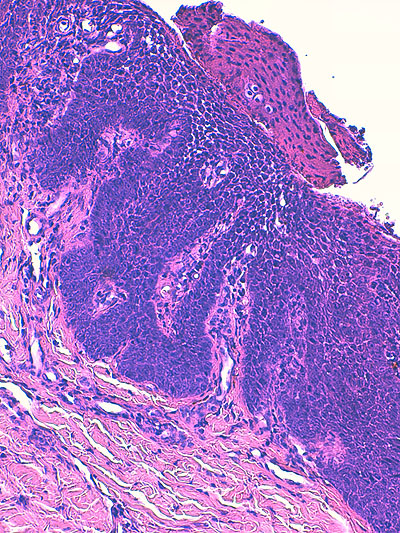

Photo 2 (Hémalun Eosine X 40) : au faible grossissement, l’épiderme revêt un aspect bleu-blanc-rouge,

bleu pour hyperplasie des couches basales, blanc pour vacuolisation des acanthocytes sous-cornés et

rouge pour parakératose de la couche cornée. Le derme est faiblement à modérément inflammatoire.

Légendes de la Photo 2 :

- Flèche bleue : hyperplasie des couches basales

- Flèche blanche : vacuolisation des acanthocytes sous-cornés

- Flèche rouge : pour parakératose de la couche cornée

- Étoile rouge : Le derme est faiblement à modérément inflammatoire

Photo 3 (Hémalun Eosine X 100) : aspect bleu-blanc-rouge à plus fort grossissement,

bleu pour hyperplasie des couches basales, blanc pour vacuolisation des acanthocytes

sous-cornés et rouge pour parakératose de la couche cornée. Le derme superficial est

le siège d’un infiltrat inflammatoire mononucléé périvasculaire modéré.

Légendes de la Photo 3 :

- Flèche bleue pour hyperplasie des couches basales

- Flèche blanche pour vacuolisation des acanthocytes sous-cornés

- Flèche rouge pour parakératose de la couche cornée

- Étoile rouge : Le derme est faiblement à modérément inflammatoire